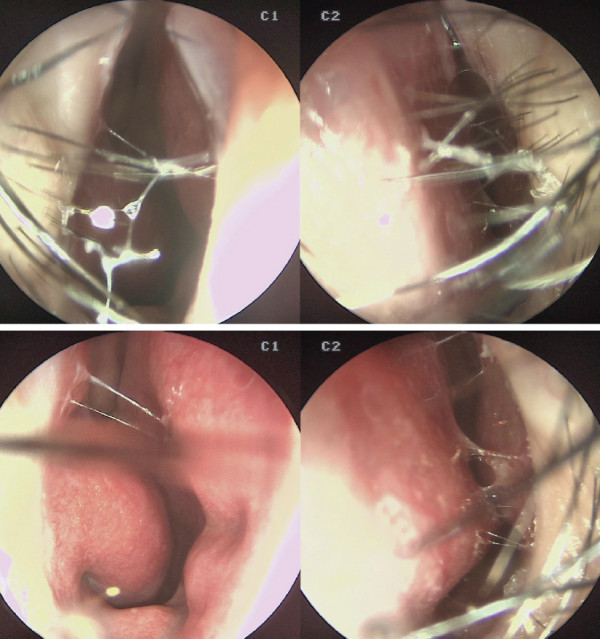

df19a8254135cde83df3de858f23ed04_1772171714_5054.jpg

선천적인 변형으로 인한 비밸브 협착도 발견되었다.

비중격 및 비 밸브 교정술, 하비갑개점막절제술 및

좌측 palateaugmentation을 계획하였다.

비중격의 미단부를 비가시(nasal spine) 및 상악에서 분리하여 좌측으로 더욱 이동시킨 후, 비중격의 bone portion에서 bone chip 일부를 채취하여 비중격의 우 측에 batten graft를 시행하였다.

수술장 소견. 비중격의 만곡과 부분적인 결손이 관찰되었다. 좌측 상악부의 결손이 확인되었으며, 비중격 미단 하단부가 비가시(nasal spine) 좌측으로 휘어 있는 상태였다. 뼈 결손은 비가시의 좌측 부위와 비중격 골부에서도 일부 관찰되었다. 상대적으로 비중격 상단부 역시 좌측으로 만곡되어 있었다.

교정된 비중격 연골의 미단부 양측에 자가늑연골을 이용한

비중격연장술을 시행하였다. 비대칭인 비익연골을 교정하기

위해 우측 비익연골은 유지하고, 좌측 비익연골만 release하여 상대적으로 좌측 비익연골을 비중격연장술에 맞추어 교정하였다. 높이 차이가 심한 경우에는 정상 측 비중격의 연장술로 연장된 연골을 일부 절제하거나, 병변 측에 rim graft 등을 시행하여 교정하기도 한다.

수술장 교정 후. 비중격 bone chip을 이용하여 우측에 batten graft를 시행하였다. 좌측 비가시 부위의 상악 결손 부위에 자가늑연골을 이식하여

함몰된 부분을 융기시켰다.

또한 좌측 병변 측 alar base를 따라 절개를 가하고,

콧구멍 바닥의 medial 쪽으로 절개를 연장하여 medial rotation flap을 통해 넓은 비익저를 개선하였다.

자가늑연골을 다져 콧등에 injection rhinoplasty

방식으로 융비를 시행하였다.